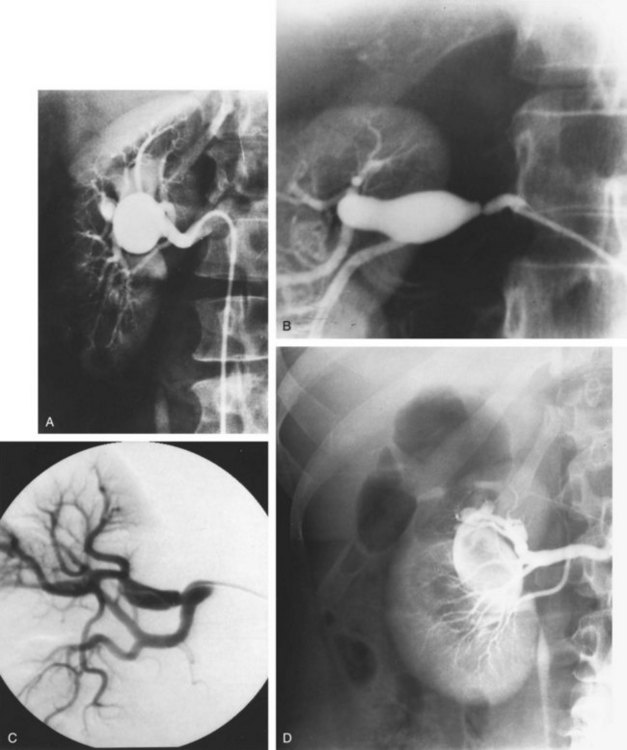

A renal arterial aneurysm is a localized dilatation of the main renal artery or its branches or both caused by weakening of the elastic tissue and media of the arterial wall. The estimated incidence of such lesions in the general population ranges from 0.09% to 0.3%. Renal arterial aneurysms may be clinically significant because of a causative relation to hypertension, associated local symptoms, or the risk of catastrophic rupture in certain situations (Novick, 1982). According to the classification of Poutasse (1975), there are four basic types of renal artery aneurysms: saccular, fusiform, dissecting, and intrarenal (Fig. 39–17).

Figure 39–17 Selective renal arteriograms demonstrate the four types of renal artery aneurysms. A, Saccular aneurysm located at the bifurcation of the main renal artery. B, Fusiform aneurysm distal to a stenotic lesion of the main renal artery. C, Dissecting aneurysm involving a renal artery branch. D, Intrarenal aneurysm.

Saccular aneurysms are the most common type and constitute about 75% of renal artery aneurysms. They generally occur at the bifurcation of the renal artery, perhaps owing to an inherent weakness in the wall of the artery at this point. Because of this location, branch arterial involvement is common. The incidence of bilateral or multiple aneurysms or both is approximately 25%. These aneurysms may become involved with secondary atherosclerotic degeneration or intramural calcification or both. Incompletely calcified aneurysms may become soft, thin, and ulcerated between zones of calcification, thus predisposing to rupture. In addition to rupturing spontaneously, saccular aneurysms may erode into the renal vein or into the renal pelvis. Mural thrombus formation may also occur within saccular aneurysms, occasionally leading to peripheral renal embolization.

Fusiform aneurysms occur as a uniform dilatation of an entire segment of the renal artery to as much as three to four times its normal diameter. These aneurysms range in length from 1 to 3 cm and are generally not calcified. They are typically found in young hypertensive patients with stenosing fibrous renal arterial disease. The fusiform aneurysm is actually a poststenotic dilatation and can involve either the main renal artery or its branches. The major complication of this lesion is thrombosis of the involved arterial segment from progressive proximal stenosing vascular disease.

A dissecting aneurysm results from a tear in the internal elastic membrane of the renal artery, and as blood flows through the opening, the intima is separated from the remainder of the arterial wall. In some patients, the dissection may reenter the lumen distally to preserve renal function. In other cases, arterial thrombosis with renal infarction or rupture with hemorrhage may occur. Dissecting aneurysms are most often complications of renal arterial involvement with atherosclerosis, intimal fibroplasia, or perimedial fibroplasia. Less commonly, such an aneurysm may occur as an extension of a dissecting aortic aneurysm.

Intrarenal arterial aneurysms are of mixed origin and may be congenital, post-traumatic, iatrogenic, neoplastic, or associated with polyarteritis nodosa. They are usually saccular or fusiform and may or may not be calcified. Intrarenal aneurysms constitute approximately 17% of all renal arterial aneurysms, and they do have the propensity for rupture. Intrarenal aneurysms that occur after blunt trauma or closed renal biopsy occasionally resolve spontaneously with expectant management.